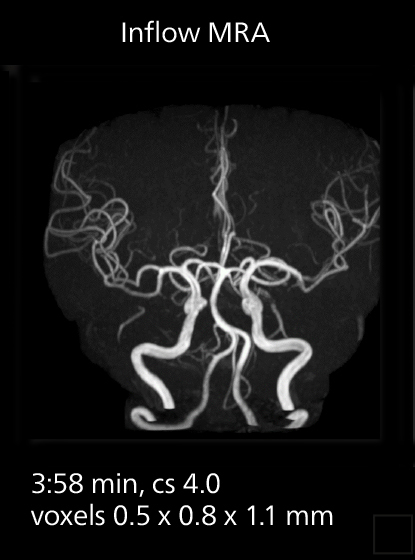

With SmartPath to Elition X, the MRCP examinations at Sannodai Hospital benefit from VitalEye: respiratory synchronization is possible without respiratory belt positioning and image quality is excellent.

SmartPath to Elition X comes with Smart Workflow technologies that support technologists and can save them time. VitalEye for touchless patient sensing is one example. “The implementation of VitalEye respiratory synchronization has had a significant impact,” says MR technologist Yoshihiro Otsu, Chief of the Radiological Department. “It not only improves workflow, but it also has increased the quality of examinations. Particularly for the large number of MRCP examinations performed in this hospital, VitalEye has increased the possibility to obtain sharp images with less blurring. Clinicians here really appreciate this improvement in MRCP image quality.” The VitalScreen on the scanner has helped reduce the risk of patient misidentification. “It allows patient information to be viewed in the magnet room when standing next to the patient,” he says. “And the automated patient centering in the magnet is very useful as well.” Apart from reducing stress for technologists, Smart Workflow helps improve respiratory synchronization and reduce examination stress for the patient.